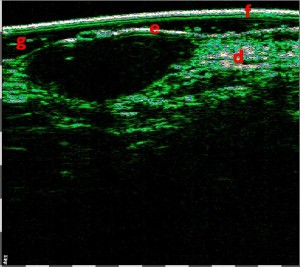

-Έγχυση Πληρωτικών Υλικών (Fillers)

-Lifting με νήματα

-Μέθοδοι θεραπείας υψηλής ενέργειας

(λέιζερ, RF-Ραδιοσυχνότητα, HIFU-Υψηλής Έντασης Εστιασμένος Υπέρηχος, κ.λπ.)